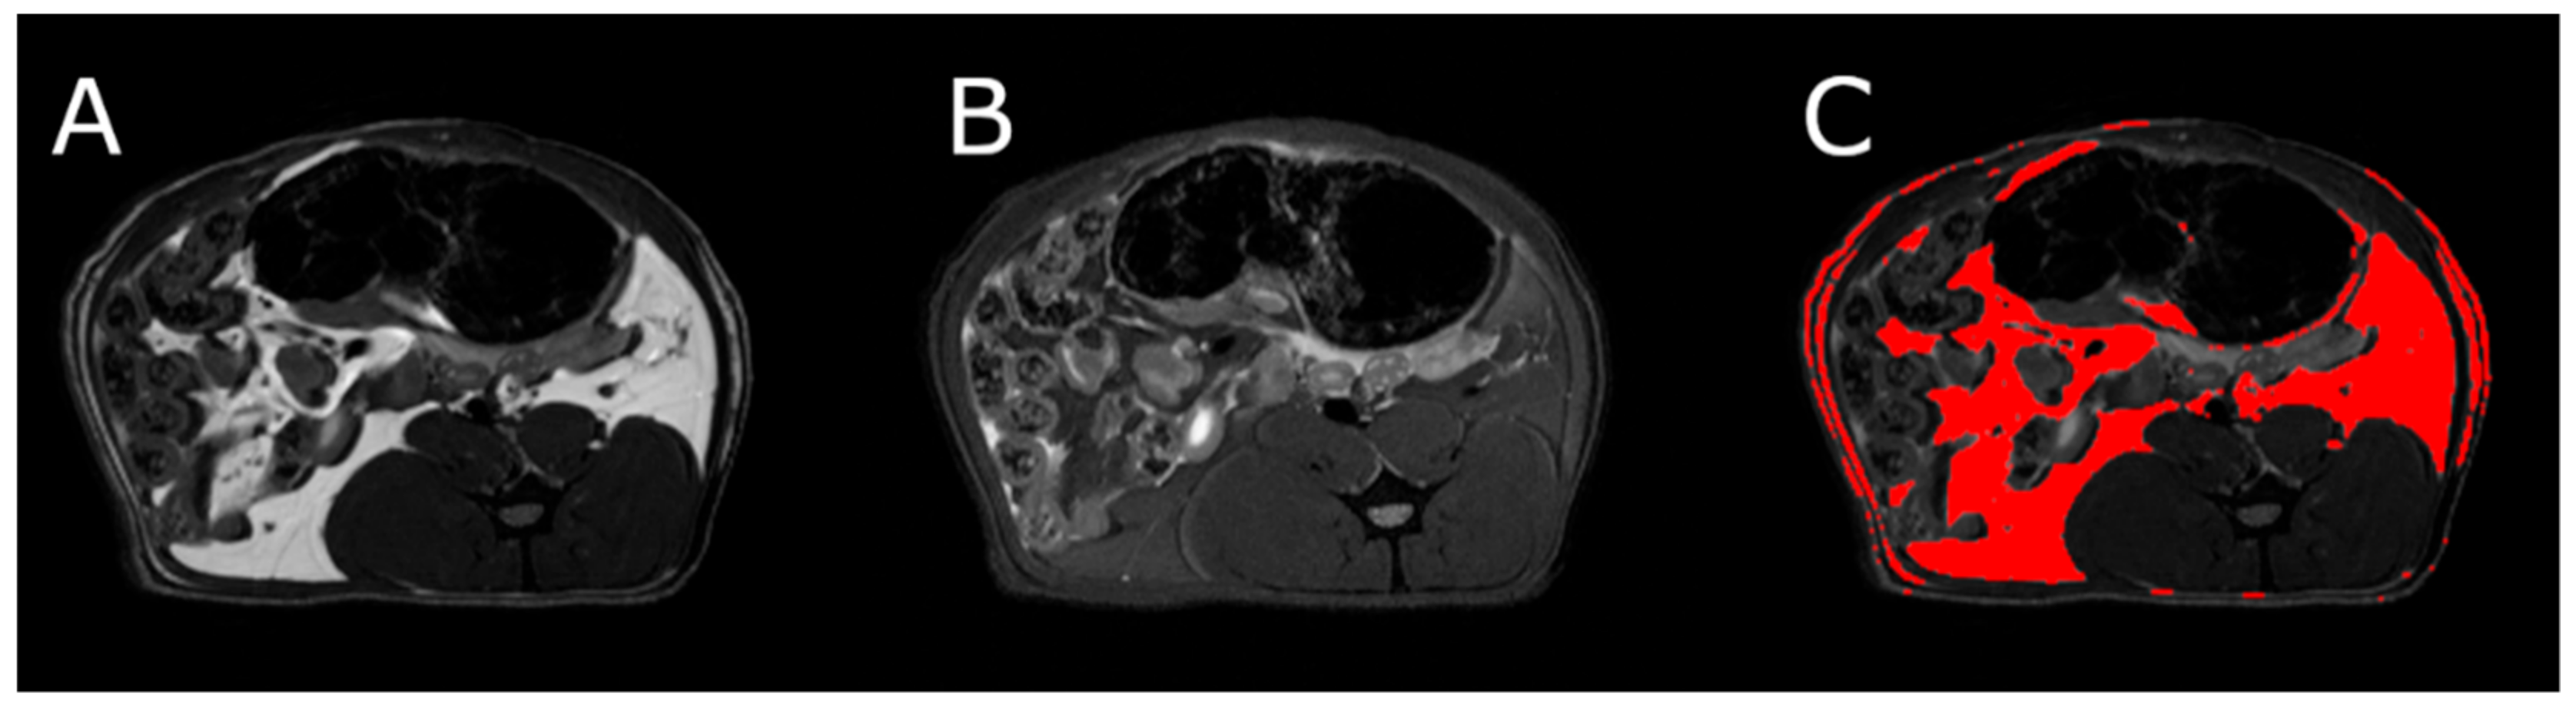

MRI measurements showed a significant reduction in the adipose tissue volume of ABA rats compared with controls (Figure 5). The mean visceral body fat reduction in the ABA rats reached 58.9% on day 6 of the experiment (Figure 6).

Figure 6.

MRI scan of female ABA rat, the cross section of the abdomen at L4 level. (A) RARE image without fat suppression; (B) fsupRARE image with fat suppression; (C) segmentation result—adipose tissue marked in red.

MRI was used to determine the volume of visceral and subcutaneous adipose tissue at the level of the L4 vertebra in healthy and ABA rats. MRI experiments were performed on a 9.4T Bruker Biospec scanner, using a Bruker T9361 transmit/receive birdcage coil with a diameter of 72 mm. Animals were euthanized with pentobarbital prior to imaging (Morbital, Biowet, Pulawy; 1–2 mL/kg b.wt.) after ketamine/xylazine premedication to obtain high-quality images devoid of any artifacts. Imaging was performed using the fast spin-echo rapid acquisition with a relaxation enhancement sequence (RARE). Pulse sequence parameters were echo time = 6.3 ms, repetition time = 2000 ms, RARE factor = 8, acquisition matrix = 256 × 256, field of view = 60 × 60 mm, and number of slices = 23. The entire abdomen from L1 to L6 was covered with 1 mm thick axial slices. Imaging was done twice, first without fat suppression (RARE) and repeated with the fat suppression module (fsupRARE) turned on. In the images obtained with the spin-echo sequence, fat appears as a bright area. This area becomes correspondingly darker when fat suppression is used. This relationship was used to find image pixels containing fat. Adipose tissue segmentation was performed using a custom-developed MATLAB script (The Mathworks, Inc.). The slice passing through the L4 vertebra in the reference anatomical image was selected for further analysis. First, the pixel values of both images were normalized to 1. The difference between the normalized RARE and fsupRARE images was then calculated—the fat containing pixels were those for which the difference image pixel value was greater than 0.2. Finally, adipose tissue volume was calculated as the product of the number of pixels containing fat and the volume of a single pixel.